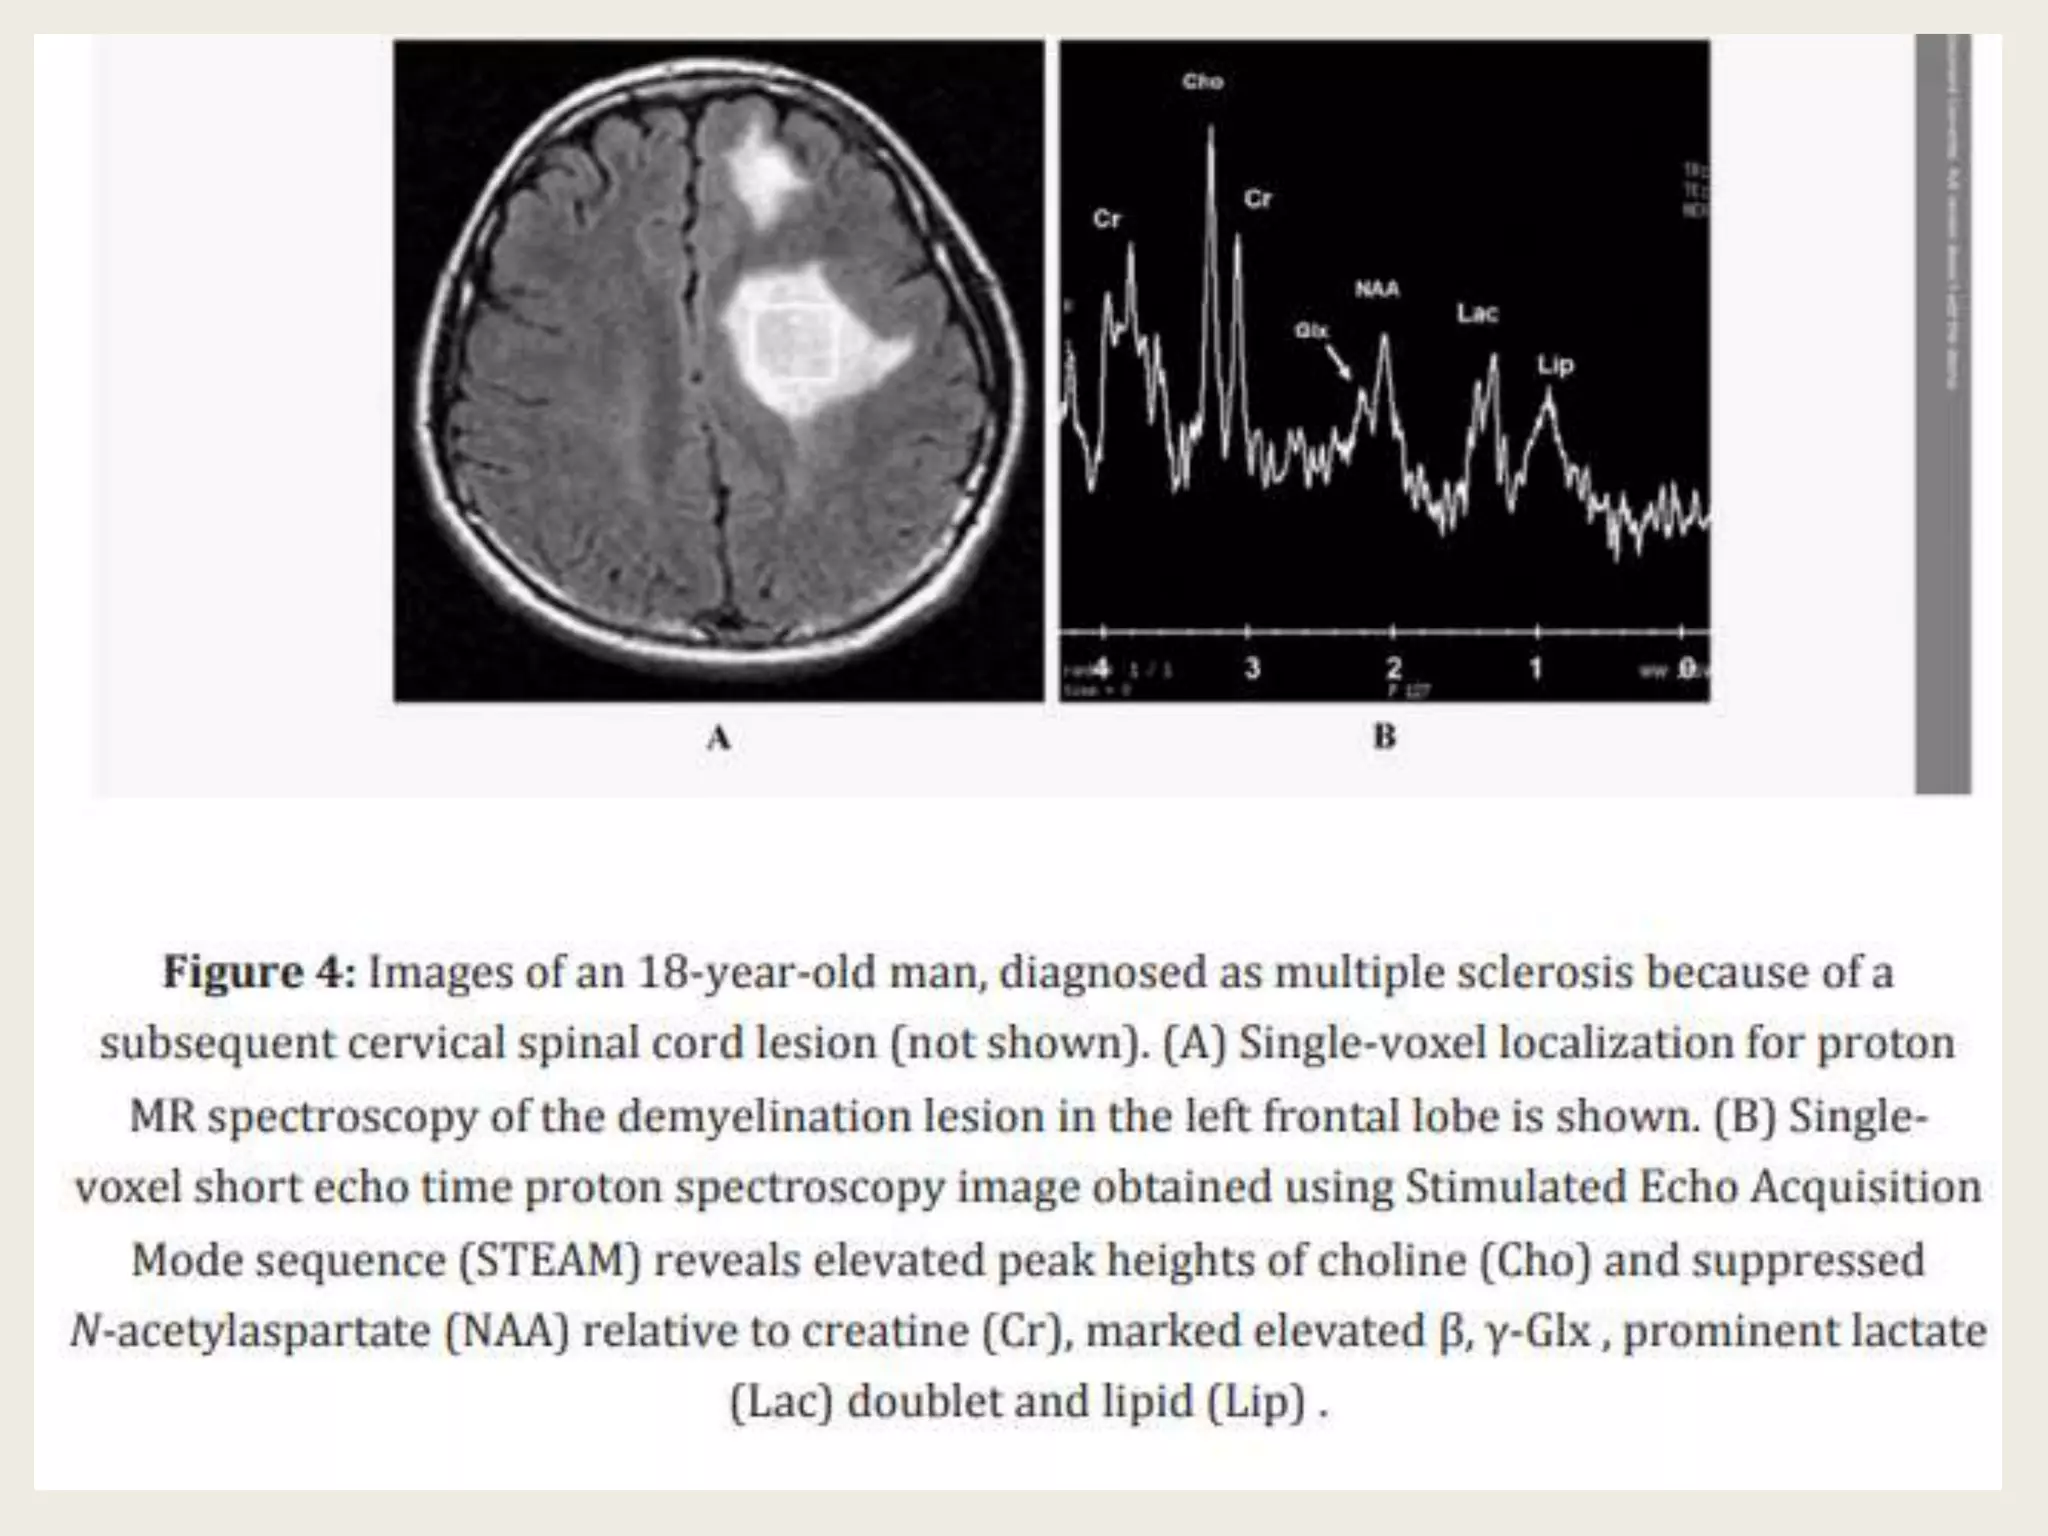

Proton magnetic resonance spectroscopy (1H-MRS) 1 H-MRS allows

the ability to measure metabolites within the MS lesions and normal

appearing brain tissues. Metabolites for 1 H-MRS include

N-acetylaspartate (NAA), choline (Cho), creatine (Cr), and myoinositol.

A decrease in NAA is associated with axonal damage. Cho is often

increased with myelin damage and inflammation. Increased Cr and

myoinositol levels can also be found in MS lesions. Amino acids which

act as neurotransmitters include glutamate, glutamine, and

γ-aminobutyric acid (GABA), can also be measured. In active enhancing

MS lesions, there is increased Cho, Cr, myoinositol, and glutamate, and

a decrease in NAA. A similar pattern of abnormal metabolites can be

detected in normal appearing brain tissues. In chronic nonenhancing

lesions, NAA is markedly decreased, myoinositol is increased and

glutamate is normal. Decreased NAA/Cr ratio within MS lesions and

normal appearing brain tissues correlates with physical and cognitive

impairment in MS, and has been shown to improve following disease

modifying therapy.